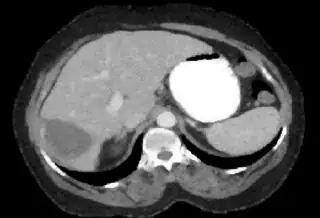

Below I apply two successive morphological openings to the image using a 3x3 circular kernel, and then apply k-means clustering to the gray levels. From your sample images and some I found on the internet, I decided to set k = 4. If you are using high-resolution images, first downsample them to dimensions ~400-600. Otherwise the morphological operation may not have a significant effect, and the k-means will be slow.

Below are some of the opened and segmented images. Of course there's more to be done in terms of

- separating out the liver region

- generalizing this to a large dataset

but hope this is at least a starting point.